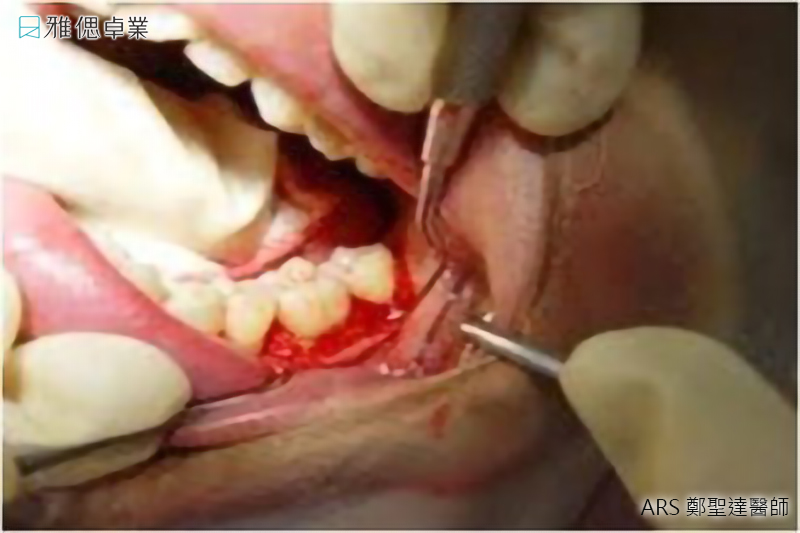

水雷射植牙手術

傳統的雷射植牙會有灼熱感,然而雅偲引進先進的水雷射科技微創植牙,不必縫合傷口,在整個治療過程中將傷口範圍縮小,讓患者感受更加舒適,更大幅度降低術後腫脹疼痛等不舒適感,也可以減少患者害怕開刀的心理負擔。

水雷射牙周手術

- 微創治療傷口更小,出血更少

- 精確及精緻切割,組織傷害更少

- 水雷射的生物刺激特性促進骨細胞分裂增生

- 促進微血管及淋巴組合,舒緩術後腫脹

- 水雷射具備的殺菌效果,降低感染機率,增加植牙成功率